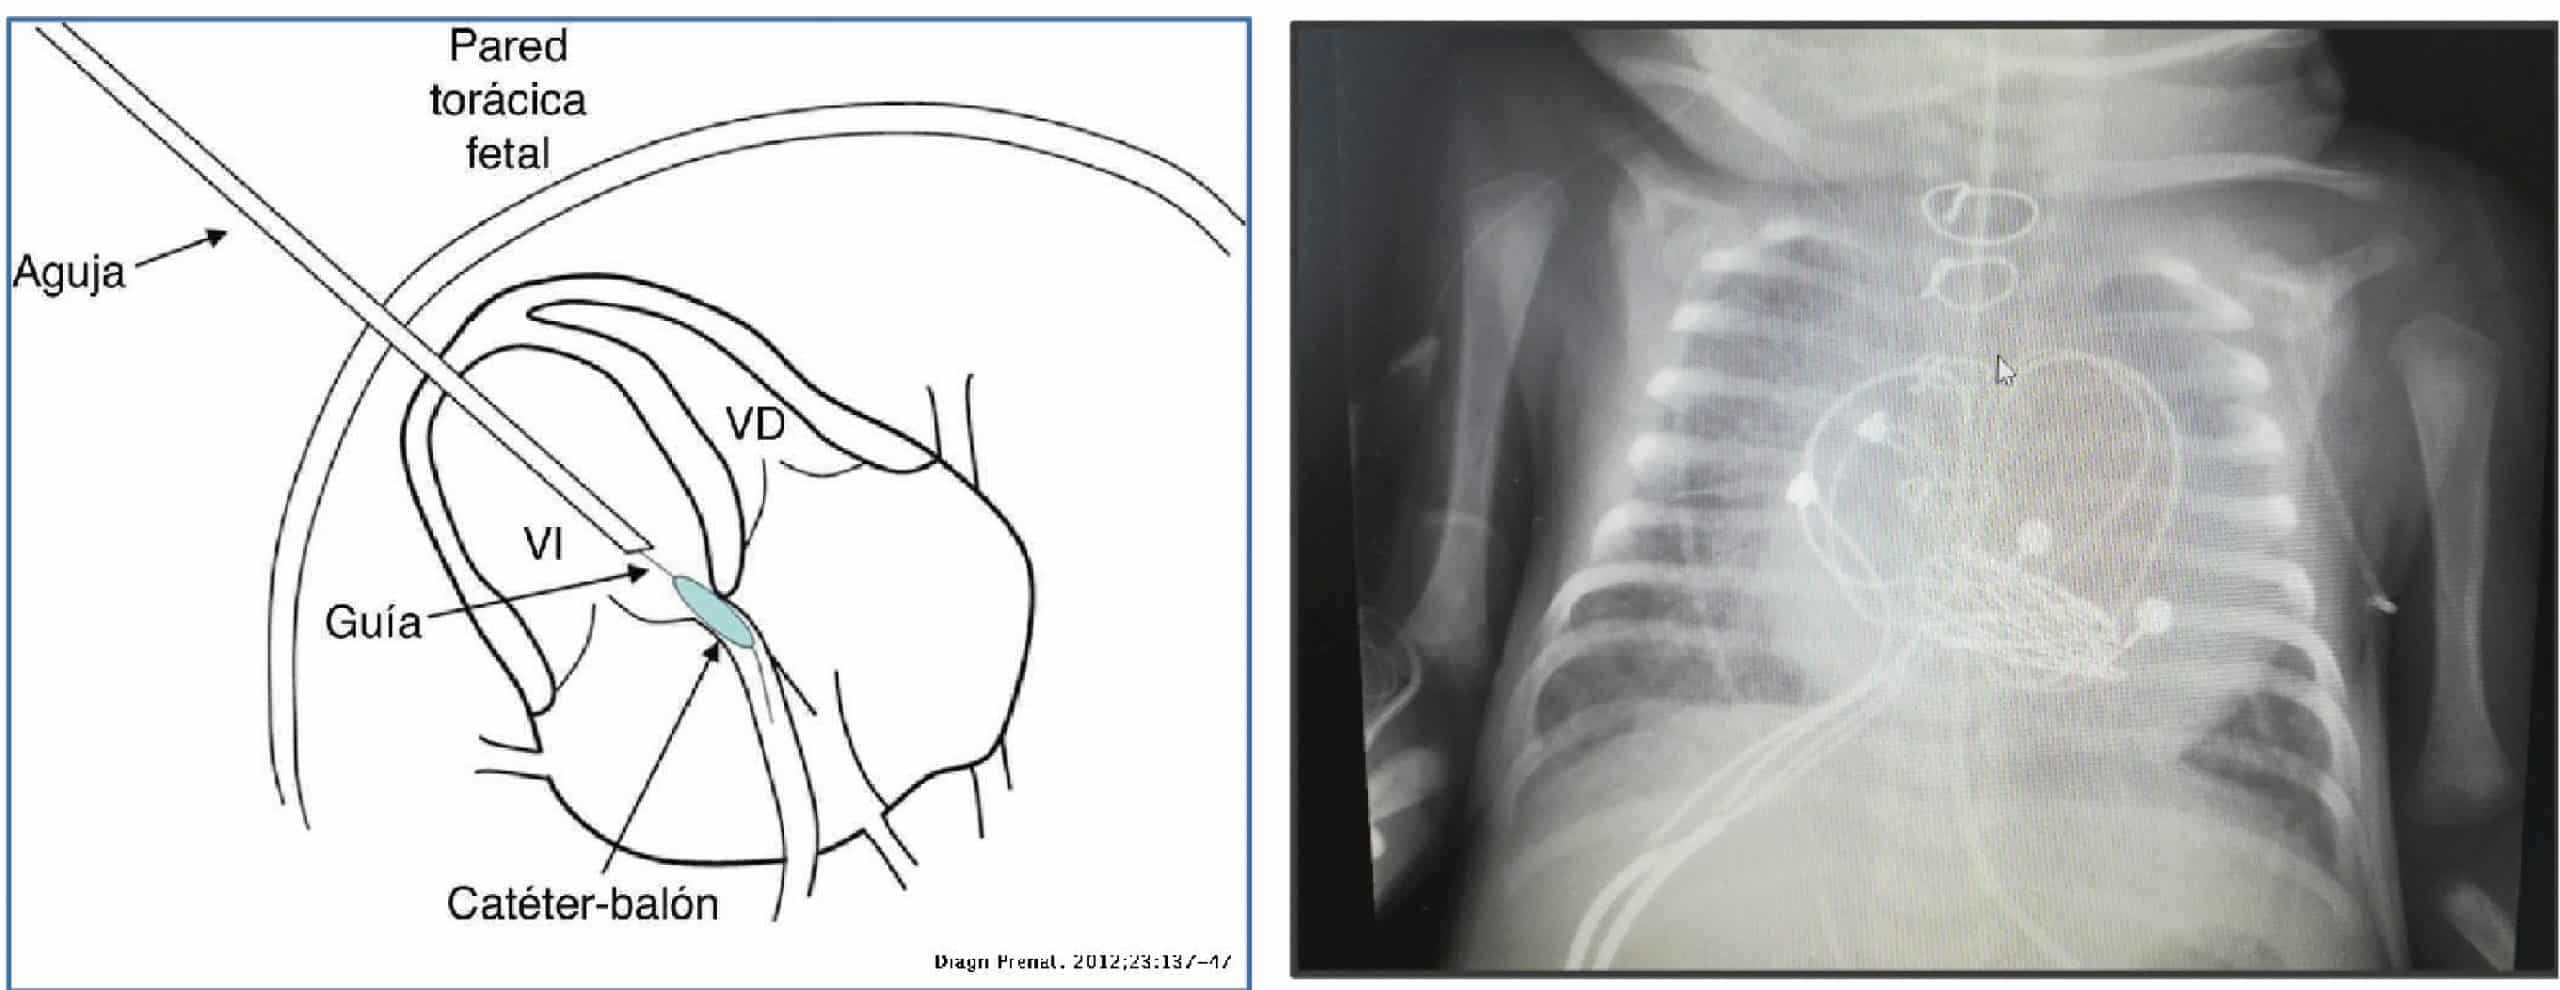

Rx de tórax

- Edema agudo de pulmón.